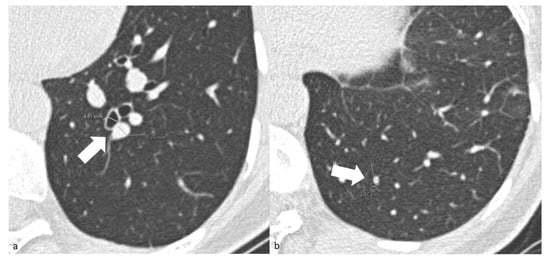

For patients in the COV-P, Bact-P, and Fung-P groups, the radiologist also measured the caliber of one segmental and one subsegmental branch of the pulmonary artery, together with their corresponding bronchial branches in the main area of lung opacification. To standardize the results, the radiologists measured the diameter only using the cross-sectional images of the segmental arterial branches 2 cm downstream of their onset and of the subsegmental branches at the level of the 7–8th generation. The adjacent bronchial branch diameter was measured, respectively, at the same level (Figure 1). To reduce inter-patient constitutional variability, the measurements of the healthy lung parenchyma were performed on the lower lobes.

Figure 1. (a) Chest axial CT images of a COV-P patient. Measurements of the segmental arterial (4.41 mm) and adjacent bronchial branches (5.76 mm) (arrow). (b) Chest axial CT images of a COV-P patient. Measurements of the and subsegmental arterial (1.56 mm) and adjacent bronchial branches (1.75 mm) (arrow) of healthy lung parenchyma of the lower left lobe.